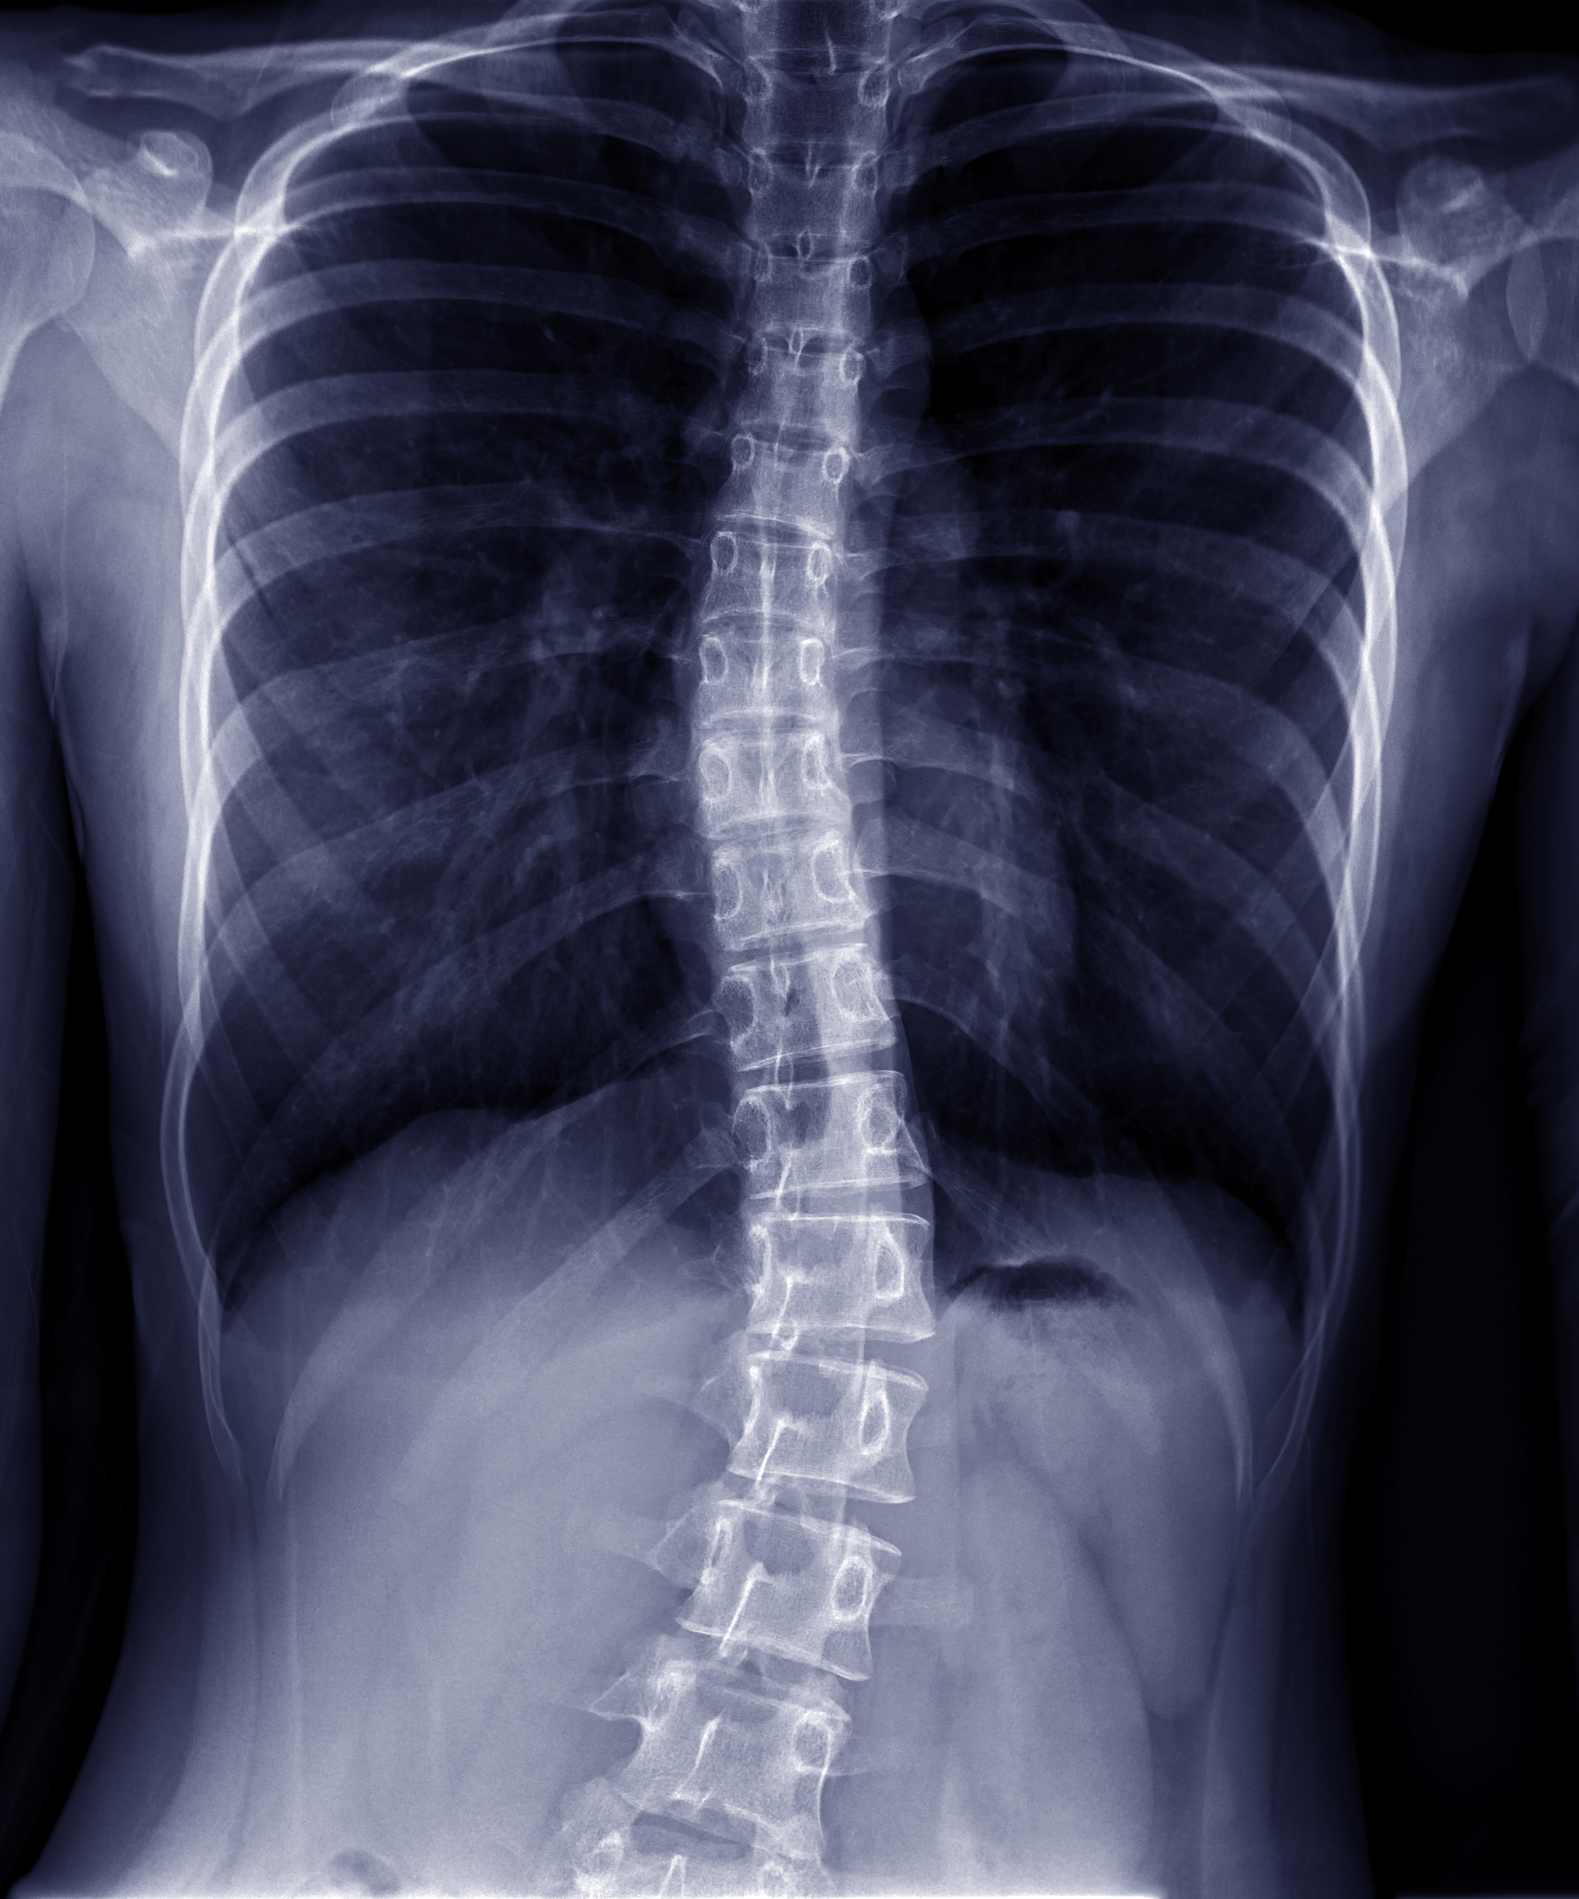

Gallery The Link Between Spinal Posture and Independence: Insights from Research and How CBP® at Symmetry Health Center Can Help